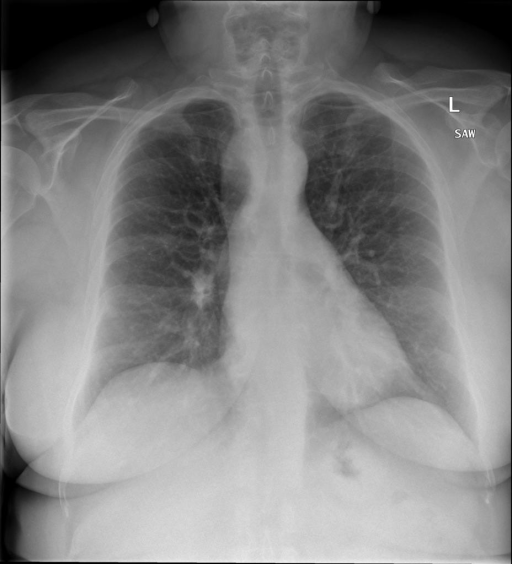

- (1)准备[诊疗报告(中文)](./data/Xray/openi-zh.json)和[X光影像](https://pan.baidu.com/s/13GBsDMKf6xBZBSHpoWH_EA?pwd=k9sh)在`data/Xray`文件夹下; - (2)开始训练: ```bash # 设置CUDA变量,主要是为了解决有时候直接训练而出现无法正确加载到显卡问题 export CUDA_VISIBLE_DEVICES=0,1,2,3 # 开始训练 bash finetune_XrayGLM.sh ``` 这里的复现过程非常简单,主要是很多过程我们都为大家准备好了,大家可以随时复现一个自己的`XrayGLM`。 ### 4.模型训练(通用) ## 效果展示 *以下效果来自于**低质量**的数据训练和权重 影像诊断: |X光影像|诊疗报告(医生)|XrayGLM| |:-|:-|:-| |![](./data/Xray/2_1.png)|根据X射线图像,心脏大小正常,肺部看起来很清晰。已经排除了肺炎、积液、水肿、气胸、腺病、结节或肿块的存在。该发现表明一切正常。换句话说,总体印象是胸部正常。|X光片显示,心脏大小正常。肺部没有气胸或胸腔积液的证据。骨骼结构看起来没有任何异常。总的来说,X光片表明没有发现急性心肺疾病的迹象。| |![](./data/Xray/2882_1.png)|X光图片显示没有扭曲的区域、可疑的骨质不透明度或胸腺积液。心脏大小轻微增大,但非常稳定。此外,没有气胸的证据,肺野也正常。总体来说,X光片显示没有急性心脏异常,但要注意轻微的心脏扩大。|X光片显示,心脏大小正常。肺部和纵隔轮廓清晰,没有气胸或胸腔积液的证据。骨骼结构完整,没有任何急性异常。| |![](./data/Xray/2577_1.png)|心影形态在正常范围内。没有急性骨质异常。有可能出现没有明显的吸水或肺实质状况的线索。没有大面积积液或气胸。有可能怀疑其有误吸或肺实质问题。为了确诊和治疗,可能需要进行适当的影像学随访。|心脏大小正常,肺部和纵隔轮廓清晰。没有急性异常或活动受限的证据。没有任何明显的气胸、胸腔积液或肺不张的迹象。此外,也没有发现任何局灶性骨质异常或其他急性疾病。| 多轮对话: |X光影像|诊疗报告(医生)| |:-|:-| |![](./data/Xray/861_1.png)|右侧主动脉突出观察到。心脏大小正常。胸部未发现明显的肺气肿、胸膜积液或可疑的肺部病变。报告指出已知右侧主动脉情况正常。| ```bash >> X光影像路径:./data/Xray/861_1.png >> 用户:这是一张什么图? >> XrayGLM:这张图片显示的是一张肺部检查的X光片。 >> 用户:请描述这张胸部X光片的诊断结果 >> XrayGLM:心脏大小正常,肺部清晰。没有急性心肺疾病的证据。 >> 用户:是否存在肺气肿? >> XrayGLM:没有肺气肿。心脏大小正常,肺部清晰。没有发现急性心肺疾病的证据。 >> 用户:平时饮食该注意什么? >> XrayGLM:饮食应该健康,均衡。建议增加蛋白质的摄入量,因为蛋白质有助于维持肌肉和骨骼的健康。多食用蔬菜、水果、全谷物以及健康的脂肪来源如橄榄油、鱼类等可以帮助获得足够的维生素和矿物质。此外,避免过度饮酒或吸烟,这些习惯可能会对心脏健康产生负面影响。 ``` ## 未来展望 1. 模型的能力更多来源于数据的支持,`OpenI-zh`作为微调数据集,其数据量足以支持研究,在更广泛的任务和性能表现上,我们认为**在大规模数据集上预训练并在高质量少量数据集上微调是一种可行的方案**; 2. 普遍意义的理解上,视觉多模态模型=视觉模型+语言模型。除了需要关注视觉模型信息与语言模型输出的搭配外,还需要**额外关注到语言模型的加强,在人机的对话中,尤其是医疗语言模型的问答上,除了专业的医疗问题回答,带有人文情怀的有温度的回答更应该是我们追寻的目标**。 3. **高精度的模型永远打不过大参数的模型**,如果在6B模型和13B模型上选择微调,请在资源充足情况下选择13B的大参数模型; ## 项目致谢 1. [VisualGLM-6B](https://github.com/THUDM/VisualGLM-6B)为我们提供了基础的代码参考和实现; 2. [MiniGPT-4](https://github.com/Vision-CAIR/MiniGPT-4)为我们这个项目提供了研发思路; 3. ChatGPT生成了高质量的中文版X光检查报告以支持XrayGLM训练; 4. [gpt_academic](https://github.com/binary-husky/gpt_academic)为文档翻译提供了多线程加速; 5. [MedCLIP](https://github.com/RyanWangZf/MedCLIP) 、[BLIP2](https://huggingface.co/docs/transformers/main/model_doc/blip-2) 、[XrayGPT](https://github.com/mbzuai-oryx/XrayGPT) 等工作也有重大的参考意义; ![](./assets/images/mpu.png) 这项工作由[澳门理工大学应用科学学院](https://www.mpu.edu.mo/esca/zh/index.php)硕士生[王荣胜](https://github.com/WangRongsheng) 、[段耀菲](https://github.com/IsBaSO4) 、[李俊蓉](https://github.com/lijunrong0815)完成,指导老师为檀韬副教授、[彭祥佑](http://www.patrickpang.net/)老师。 *特别鸣谢:[USTC-PhD Yongle Luo](https://github.com/kaixindelele) 提供了有3000美金的OpenAI账号,帮助我们完成大量的X光报告翻译工作 ## 免责声明 本项目相关资源仅供学术研究之用,严禁用于商业用途。使用涉及第三方代码的部分时,请严格遵循相应的开源协议。模型生成的内容受模型计算、随机性和量化精度损失等因素影响,本项目无法对其准确性作出保证。即使本项目模型输出符合医学事实,也不能被用作实际医学诊断的依据。对于模型输出的任何内容,本项目不承担任何法律责任,亦不对因使用相关资源和输出结果而可能产生的任何损失承担责任。 ## 项目引用 如果你使用了本项目的模型,数据或者代码,请声明引用: ```bash @misc{wang2023XrayGLM, title={XrayGLM: The first Chinese Medical Multimodal Model that Chest Radiographs Summarization}, author={Rongsheng Wang, Yaofei Duan, Junrong Li, Patrick Pang and Tao Tan}, year={2023}, publisher = {GitHub}, journal = {GitHub repository}, howpublished = {\url{https://github.com/WangRongsheng/XrayGLM}}, } ``` ## 使用许可 此存储库遵循[CC BY-NC-SA](https://creativecommons.org/licenses/by-nc-sa/4.0/) ,请参阅许可条款。